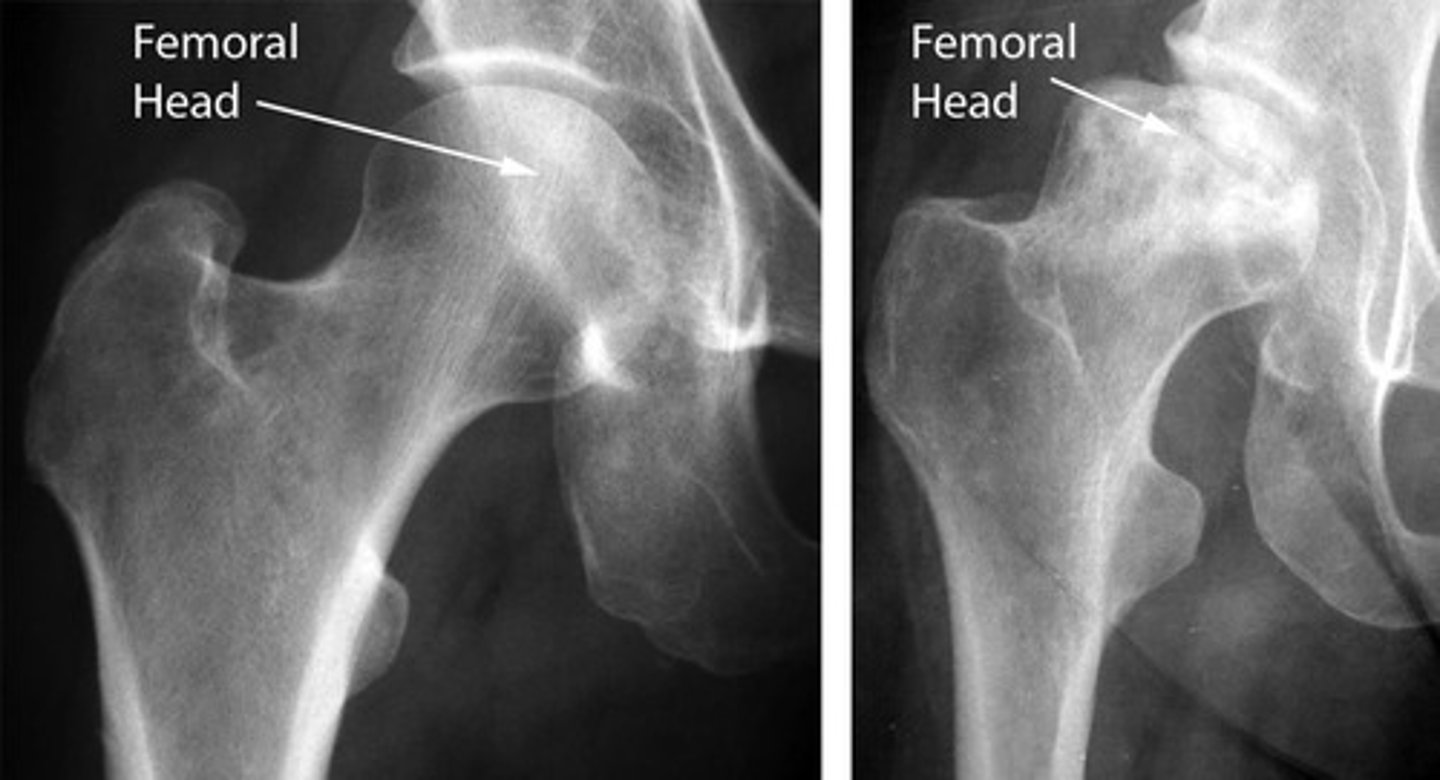

avascular necrosis

bone death due to lack of blood supply, often in proximal and distal femoral head, X-Ray is most used and MRI is most sensitive modality

caused by trauma, long term alcohol use, long term glucocorticoid use, sickle cell anemia, pediatric disorders

findings: devascularized bone becomes denser and more sclerotic